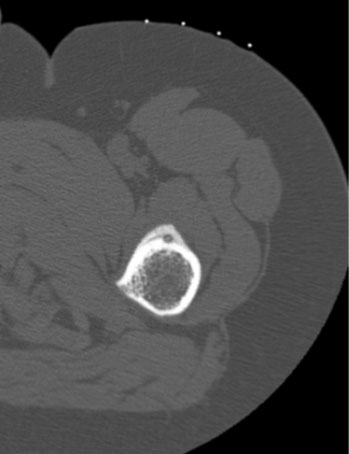

Bu yöntem hassas ve ağrılı bir işlem olduğu için görüntüleme eşliğinde (sıklıkla tomografi (özellikle osteoid osteoma uygulamalarında) nadiren floroskopi dediğimiz portabl röntgen eşliğinde) ve anestezi altında (lokal değil spinal/epidural ya da genel anestezi) uygulanmaktadır.

Özellikle kalça çevresi ve uyluk gibi derin yerleşimli osteoid osteoma vakalarında açık cerrahi ile tümörün tespiti zor olabileceği için atlama riski vardır. Ayrıca açık cerrahi ile yara problemi ve kemikte oluşacak harabiyete bağlı kırık riski yüksektir. Osteoid osteoma da RF ablasyon işlemi tomografi altında yapılacağı için atlanma riski yok denecek kadar azdır ve kapalı bir işlem olduğundan (<1cm) yara sorunu son derece nadirdir.

Elektrotun osteoid osteomada nidusa en yakın yere diğer iyi huylu tümörlerde ise tümörün merkezine yerleştirilmesi işlemin etkisi ve tedaviye yanıtı açısından son derece önemlidir. İşlem esnasında ısı kademeli olarak 90 dereceye kadar artırılıp 6-7 dakika süreyle yakma işlemi gerçekleştirildikten sonra tekrar kademeli olarak düşürülür.